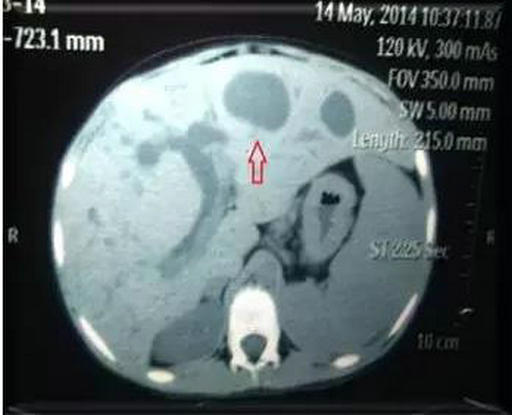

术前多发肝内胆管囊样扩张

李晓勇教授及主管医生陈艳军副主任医师热情地接待了小夏及家人,在全面了解病史、详细检查之后,小夏的病情让经历了种种疑难病症的李晓勇教授陷入了深思。小夏的肝脏明显增大,弥漫性肝硬化,肝中叶肿物较大,80mm×70mm左右,并且肿物与左右肝管关系密切,门静脉主干及左右支明显受压。